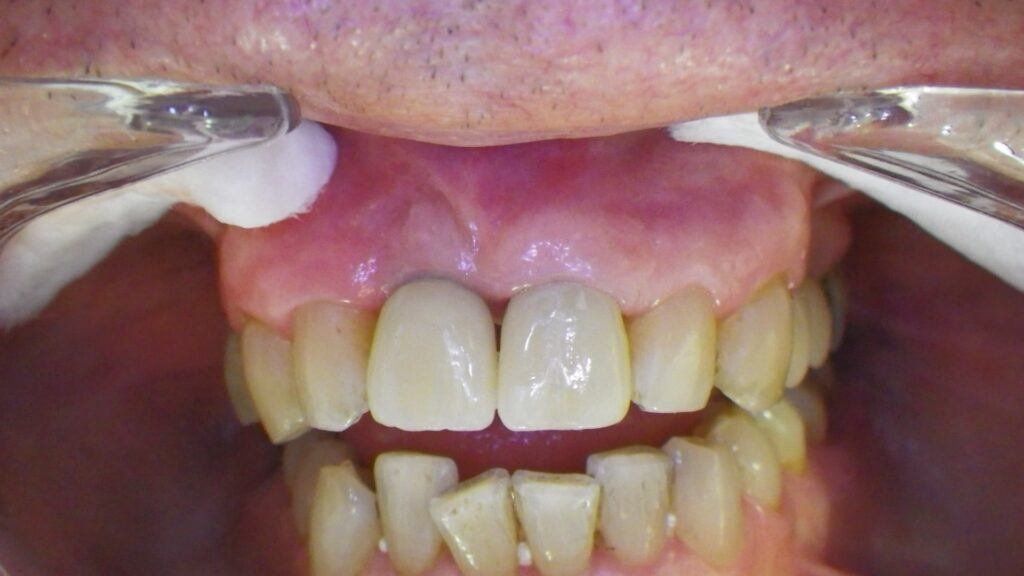

Restauración de incisivos

Este paciente llegó al consultorio con reabsorción dentinaria (pérdida de la estructura del diente).